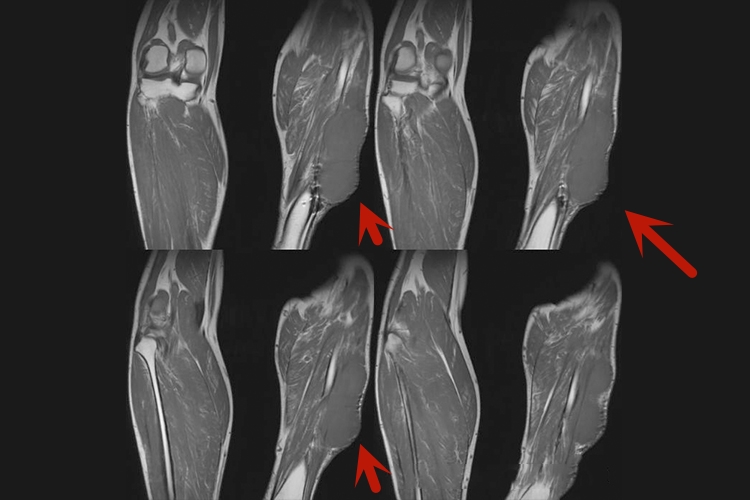

横纹肌肉瘤:好发于头部、颈部、泌尿生殖道及腹膜后。病程短,主要症状为痛性或无痛性肿块,皮肤表面红肿,皮温高。肿瘤大小不等,质硬,就诊时多数肿块固定。肿瘤生长较快,可有皮肤破溃、出血。